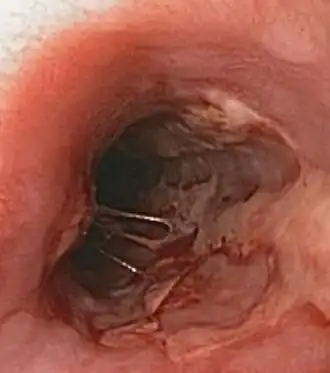

Герпетический эзофагит Герпетический эзофагит характеризуется болезненным или затруднённым глотанием. Часто протекает на фоне иммунодефицитов (например ВИЧ/СПИД) или в посттрансплантационном периоде.